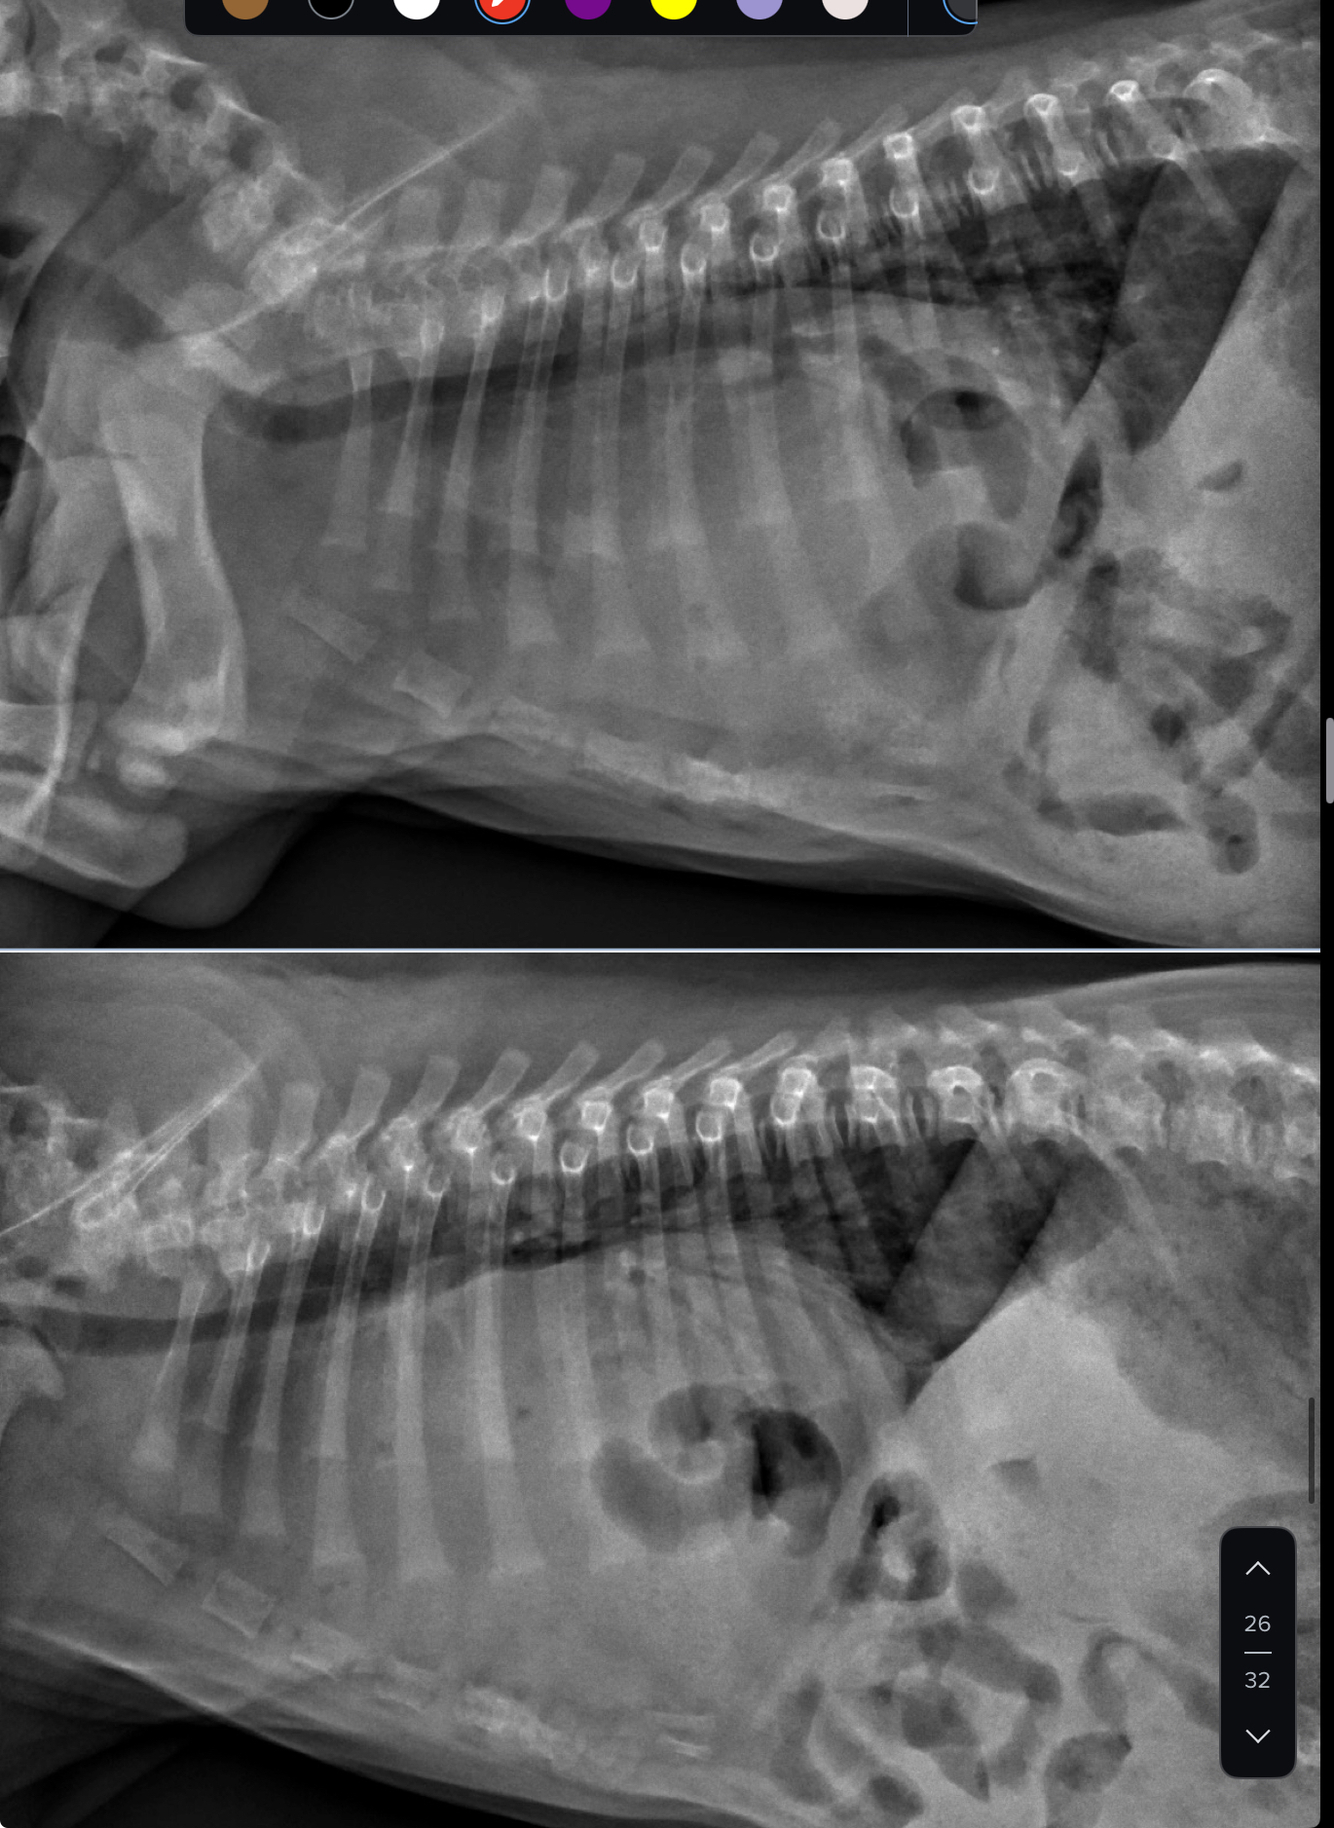

what wrong

left atrial enlargement